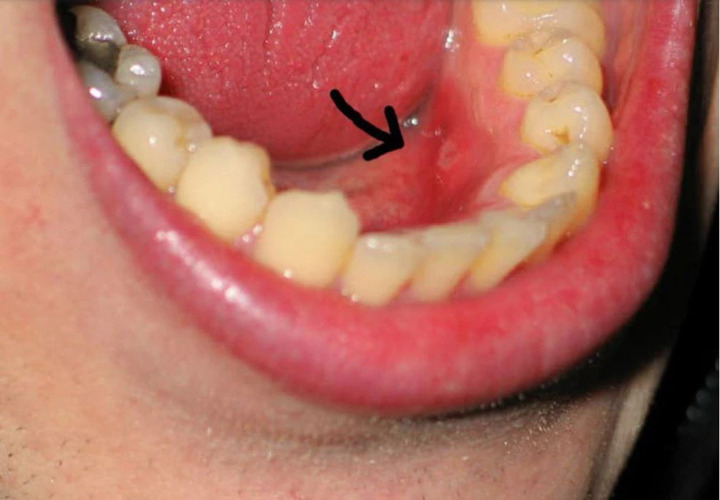

Ung thư khoang miệng triệu chứng dễ nhầm với nhiệt miệng (Ảnh minh họa)

Một số triệu chứng dễ gặp nhưng dễ bị nhầm lẫn với nhiệt miệng gồm: Vết loét trong miệng kéo dài; mảng trắng hoặc đỏ bất thường trên niêm mạc miệng, lưỡi hoặc lợi; Đau âm ỉ hoặc rát nhẹ ở lưỡi, lợi, má trong; Chảy máu nhẹ không rõ nguyên nhân khi đánh răng hoặc ăn uống.

Các bác sĩ lưu ý, điểm quan trọng nhất để phân biệt với bệnh lành tính là tính chất kéo dài và không đáp ứng với điều trị thông thường. Vì vậy, bất kỳ tổn thương nào trong khoang miệng tồn tại quá 2 - 3 tuần đều cần được kiểm tra chuyên khoa càng sớm càng tốt.